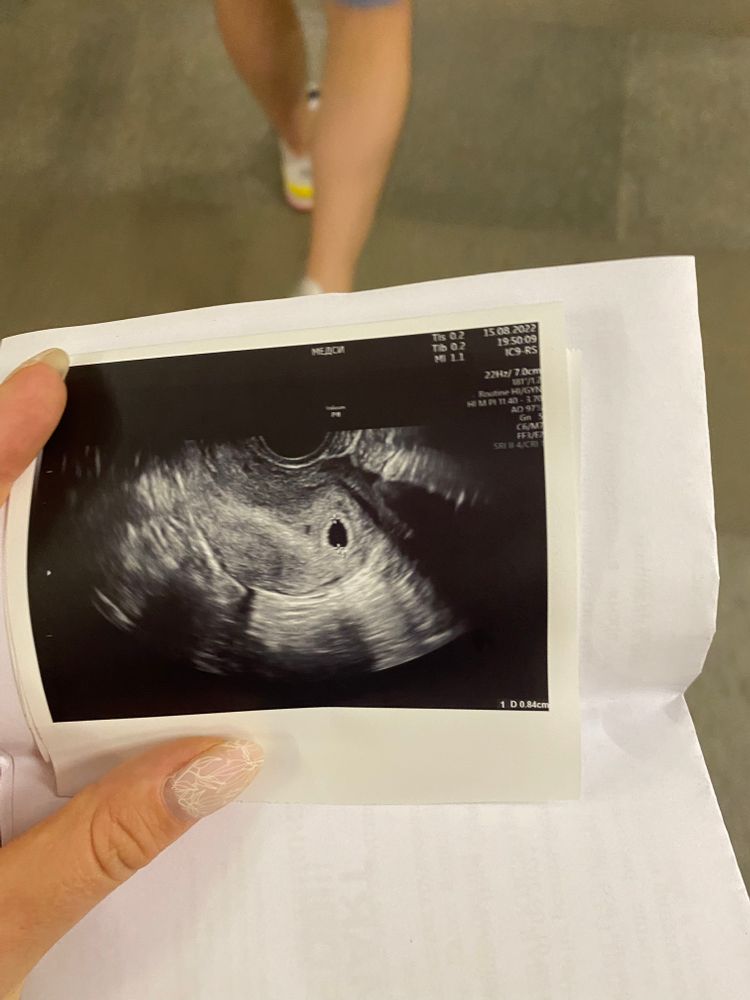

Первое узи

Всем привет! Сходила на узи, сказали срок маленький, размер ПЯ 8.4 мм. Желточного мешочка нет.

По месячным срок 5+5 недель, но есть ощущение, что была поздняя овуляция.